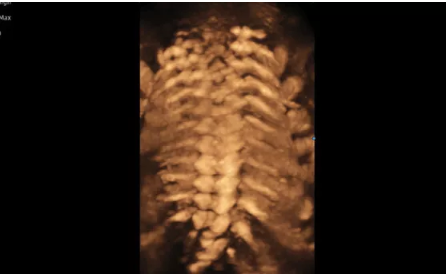

3D/4D成像方面,Hera i 10通過結(jié)合先進的圖像渲染技術(shù),著重加強了邊緣和小結(jié)構(gòu)的可視化能力。